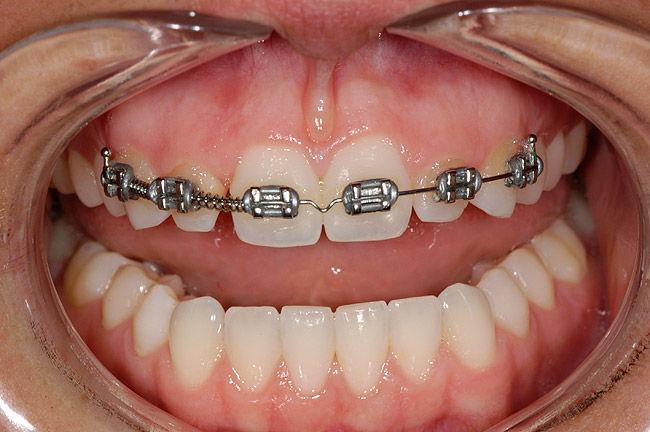

Figure 8 A lack of harmony in tooth size and position for an adult patient treated with cuspid substitution to replace the congenitally missing maxillary lateral incisors.

Figure 8

Figure 10 Orthodontics were utilized to more evenly distribute spaces and widen the arch form.

Figure 10